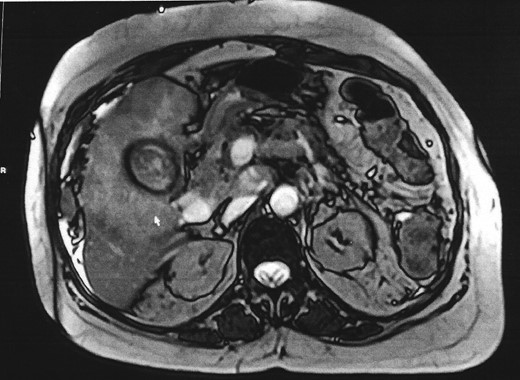

To fully assess for management options, the regional hepatobiliary multidisciplinary meeting recommended magnetic resonance cholangiopancreatography (MRCP) and a liver biopsy. MRCP showed extensive gallbladder tumour involving adjacent parenchyma (Fig. 3), dilated intrahepatic bile ducts with a trace peri-hepatic fluid, scattered satellite liver metastases, bilateral lung metastases and extensive peri-portal, portocaval and upper retroperitoneal lymph nodes. US-guided liver biopsy confirmed metastatic adenocarcinoma consistent with a pancreatico-biliary system, gall bladder or upper gastrointestinal tract primary site. These results negated any active management of the condition and the patient was therefore discharged on a palliative care pathway. She was admitted 2 weeks later with diffuse abdominal pain, ascites, which was subsequently drained, but she clinically deteriorated and passed away 4 weeks later.

MRCP shows gallbladder fundus with a T2 weighted hypo intense rim.